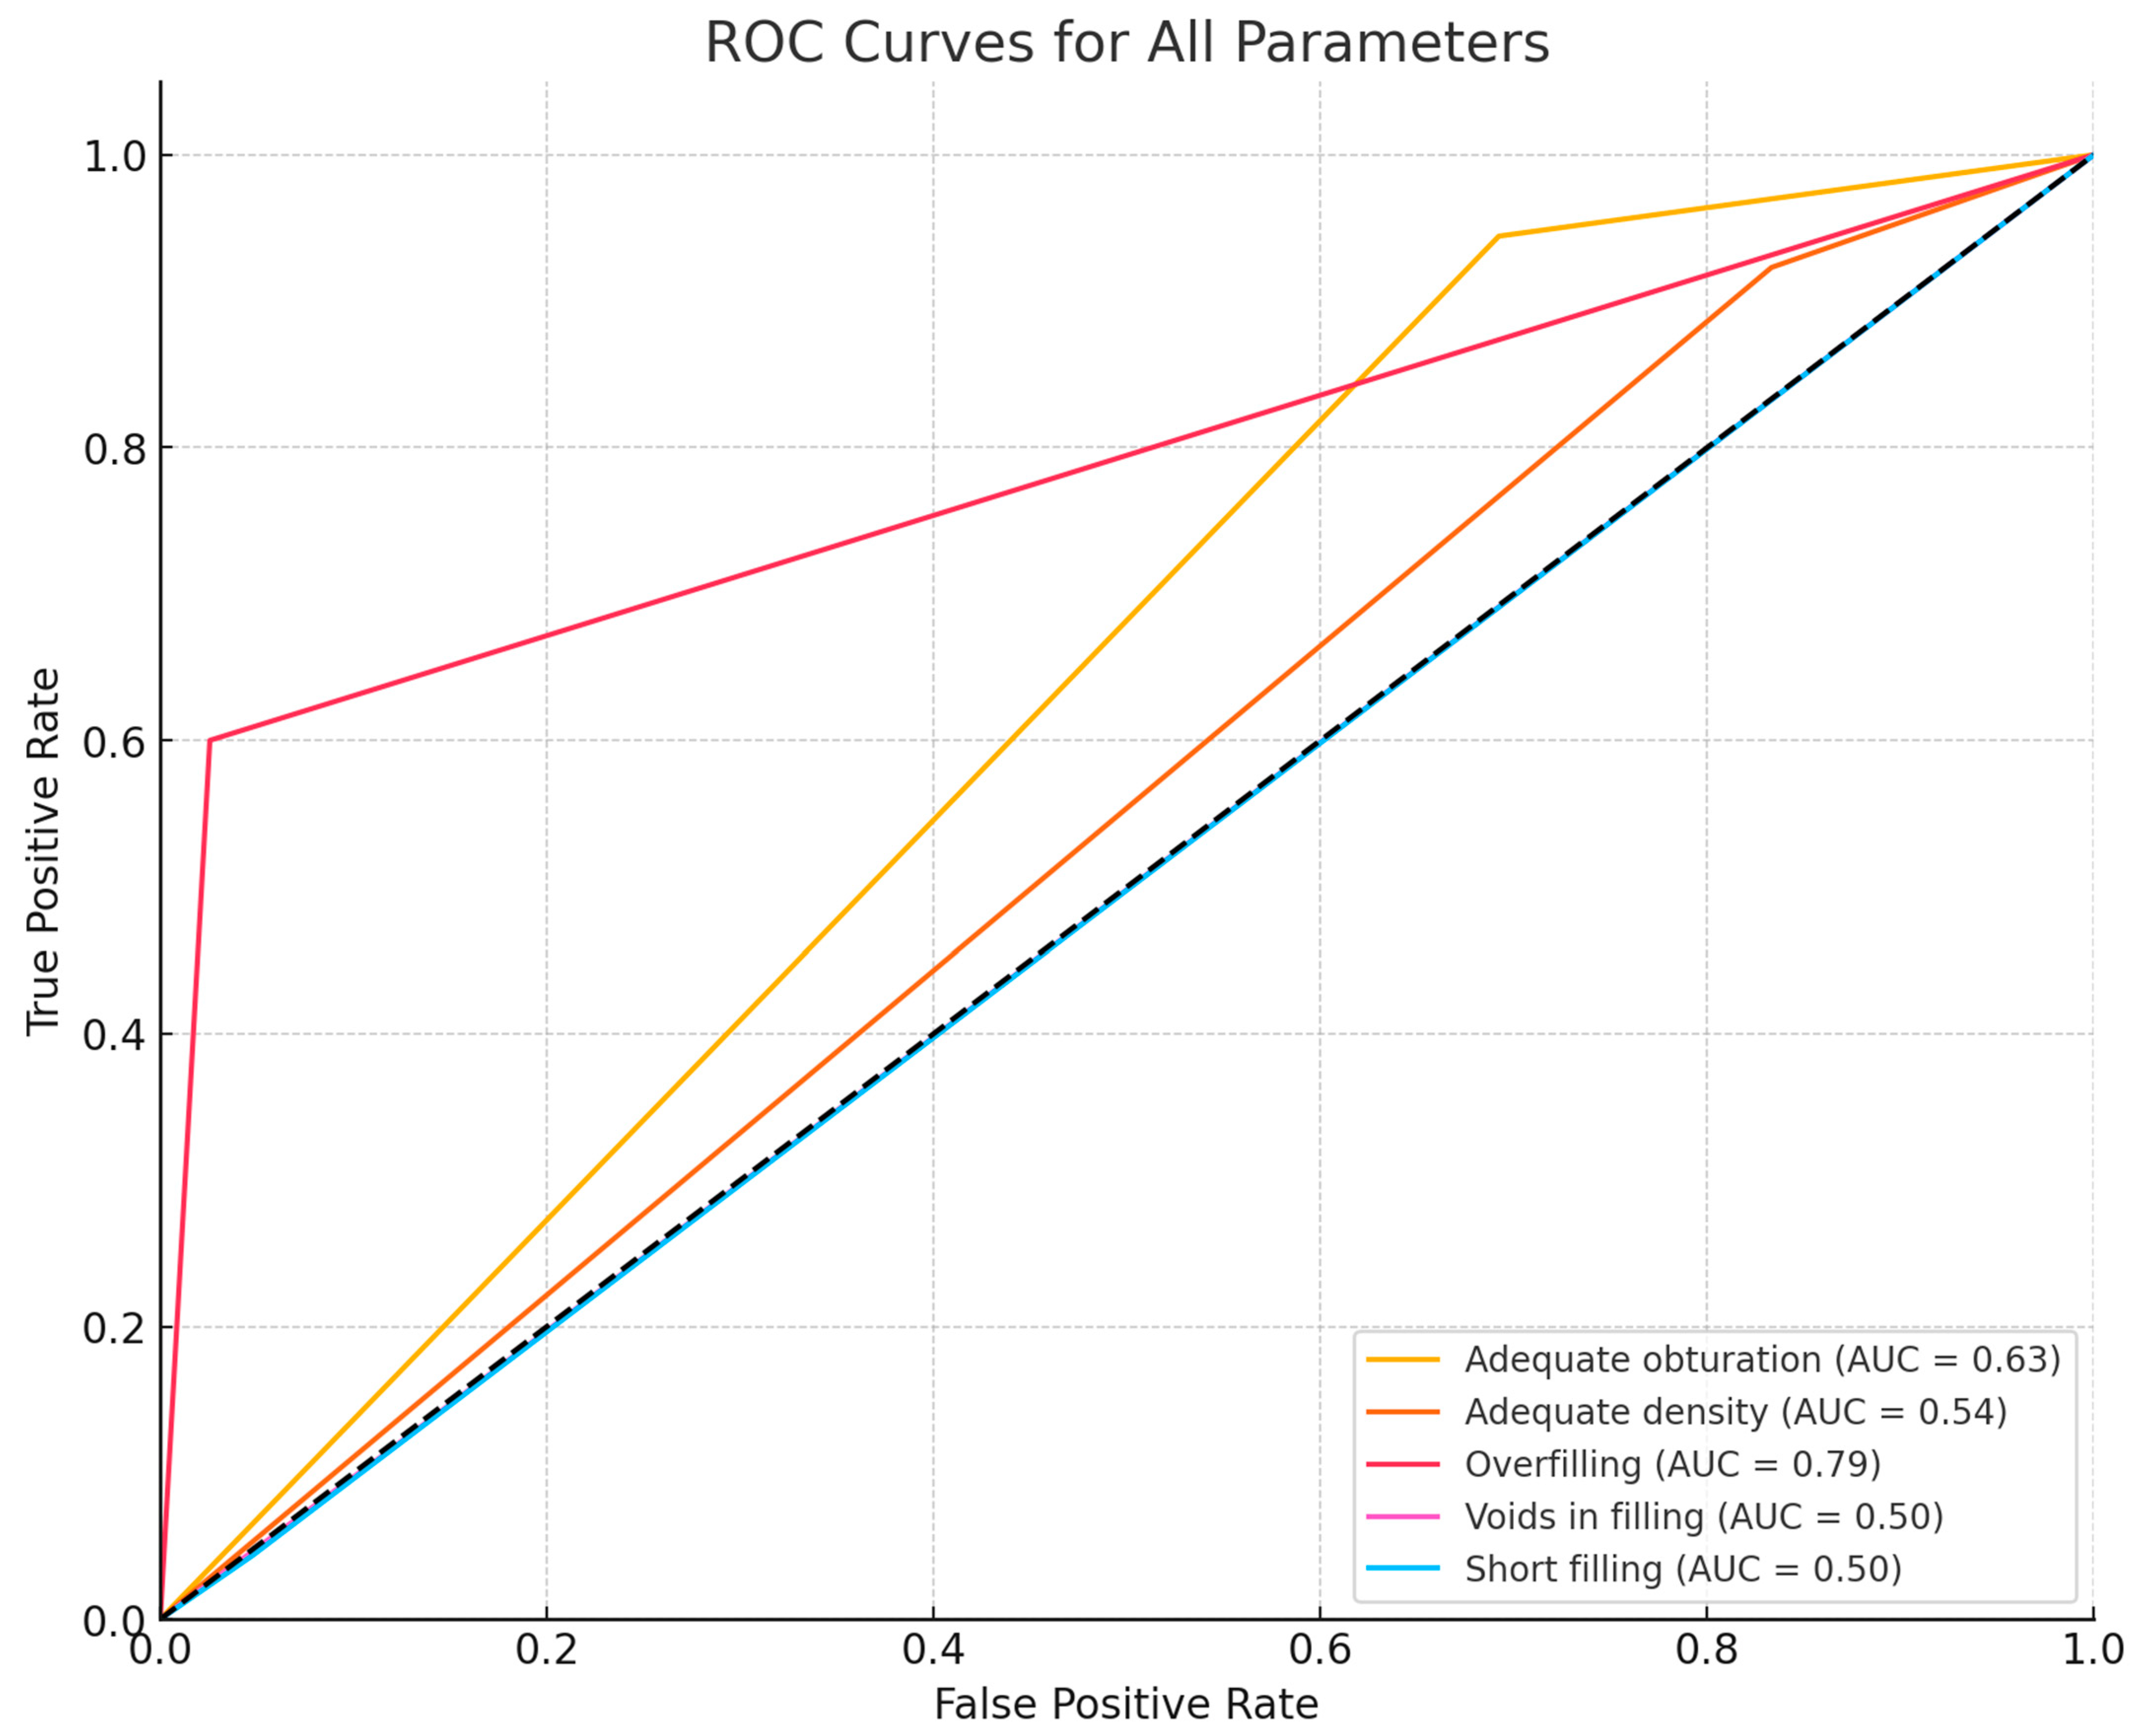

3.2. Diagnostic Accuracy Parameters

| Parameter | Sensitivity | Specificity | Accuracy | PPV | NPV | F1 |

|---|---|---|---|---|---|---|

| Filling probability | 90.70% | 100.00% | 90.70% | 100.00% | 0.00% | 95.12% |

| Obturation adequacy | 94.12% | 30.77% | 55.81% | 47.06% | 88.89% | 62.75% |

| Density adequacy | 96.00% | 16.67% | 62.79% | 61.54% | 75.00% | 75.00% |

| Overfilling | 60.00% | 97.37% | 93.02% | 75.00% | 94.87% | 66.67% |

| Voids in filling | 11.11% | 88.24% | 72.09% | 20.00% | 78.95% | 14.29% |

| Short filling | 4.35% | 100.00% | 48.84% | 100.00% | 47.62% | 8.33% |